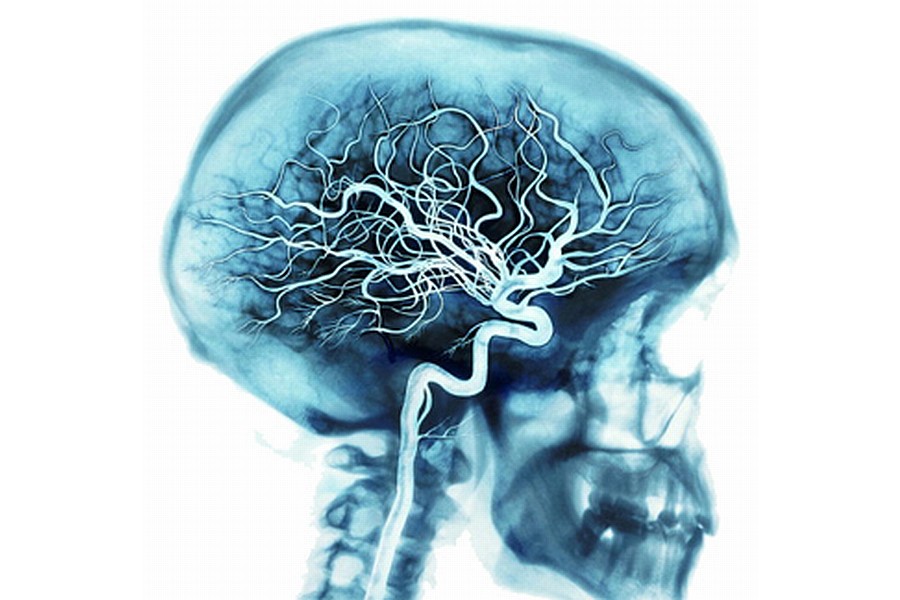

Nádory si vyrábějí vlastní cévy

Nádory se nespoléhají jen na krevní cévy, které si „vypůjčí“ od svého hostitele. Dvě nezávislé studie ukazují, že přinejmenším mozkové nádory jsou schopné vytvořit si své vlastní cévy. To je zřejmě také důvodem, proč se jeden typ léků proti rakovině nesetkal s očekávaným úspěchem.

Dlouho se zdálo, že nádory jsou závislé na kyslíku a živinách, které jim dodávají krevní cévy hostitele. Tato závislost se stala podkladem pro vývoj protinádorového léku Avastinu, do kterého se vkládaly velké naděje. Lék, který bránil růstu nových cév, a tím měl také bránit růstu nádoru, se však stejně jako jiné inhibitory angiogeneze neosvědčil – v nejlepších případech prodloužil pacientům život o několik měsíců. Dvě nezávislé studie (jedna z Itálie a druhá ze Spojených států) teď vysvětlují, proč byl neúspěch nevyhnutelný.

V obou případech vědci pracovali se vzorky agresivního mozkového nádoru glioblastomu. A v obou případech zjistili, že krevní cévy uvnitř nádoru obsahují genetické markery, které jsou pro nádorové buňky charakteristické. Soudili, že nádor nevyužil jen cévy ve svém okolí, ale některé si vytvořil na vlastní pěst. Vědci pak podle markerů identifikovali subtyp nádorových buněk podobných kmenovým buňkám. Ten má – stejně jako kmenové buňky – schopnost vyvinout se do různých typů dospělých buněk. V tomto případě z kmenových nádorových buněk vznikl jak samotný nádor, tak jeho vlastní krevní cévy. Dokazují to experimenty na Petriho miskách, během kterých tyto buňky vytvořily krevní cévy, a pokud byly přeneseny do mozku laboratorní myši, daly vzniknout glioblastomu pocházejícímu z lidských buněk. Vědci také v jedné studii zkusili přidat k buněčné kultuře lék Avastin a zjistili, že na růst krevních cév z nádorových kmenových buněk nemá prakticky žádný vliv.

V druhé studii zase vědci selektivně zahubili vlastní cévy nádoru. Nádor se zmenšil, což potvrdilo, že je na svých vlastních cévách závislý. Tato závislost je však zřejmě velmi variabilní - u jednotlivých vzorků nádorů se podíl buněk krevních cév odvozených od nádorových buněk pohyboval mezi 20 a 90 procenty. Jestli se „samovaskularizace“ týká jen glioblastomů, zatím není jasné, i když existují náznaky, že by se mohl vyskytovat také u dalších typů nádorů.

Vysoká funkční plasticita nádoru z praktického hlediska znamená, že jeden zásah proti cévám nádoru nestačí. Nutná je kombinovaná terapie, která zasáhne cévy hostitele (jako Avastin) i kmenové nádorové buňky, ze kterých vznikají vlastní cévy nádoru.